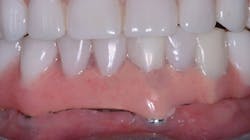

The most well-known implant-supported fixed restoration concept for edentulous patients was taught by Per-Ingvar Brånemark, MD, PhD, more than 30 years ago. Typically, six implants were placed on each arch, located anterior to the sinus on the maxillary and anterior to the mental foramen on the mandibular. When the implants had integrated into the bone over several months, a prosthesis was screwed onto the implants. Cantilevers were extended on each side of the arch, about one centimeter distal to the implant-supported portion of the prosthesis. The prostheses usually included 12 teeth, including the first molar only distally. Overall, these prostheses served well (figure 1). If one or two implants failed, which occasionally happened, the prostheses usually were still viable and functioned adequately.

Figure 1: Patient with maxilla restored with the previous popular concept using six implants as described in the narrative